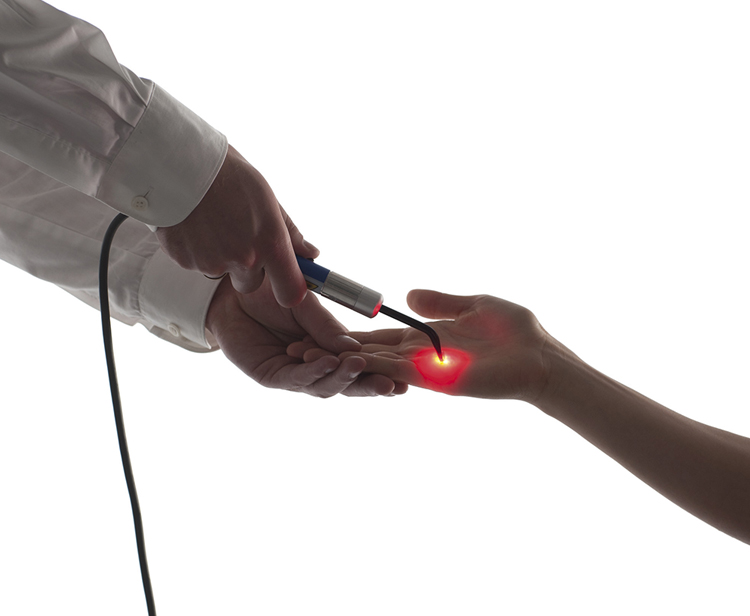

לייזר בעוצמה נמוכה (PhysioGo Lite)

מאיץ ריפוי רקמות ומפחית דלקות, מצוין לאחר פציעות וניתוחים